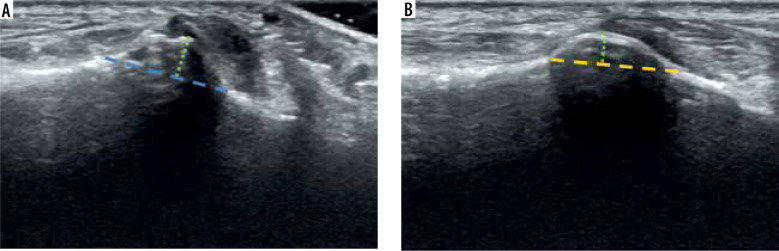

目的:本研究旨在探讨超声波是否是测量腓骨结节大小的可靠而准确的工具:本研究测量了 100 名无症状患者的腓骨结节宽度、长度和高度,并将测量结果与之前的足部 X 光片(如有)和之前报道的解剖数据进行了比较。这项研究还评估了超声波作为测量工具的内部和相互之间的可靠性:结果:我们的研究结果表明,超声波对腓骨结节的测量结果与文献报道的数值以及之前的X光片上有关宽度的测量结果一致。观察者内部和观察者之间的测量结果都是可靠的:本研究强调了超声成像作为一种测量腓骨结节的有前途的工具的潜力,它有助于更好地了解腓骨肌腱疾病。

Purpose: The aim of this study was to investigate if ultrasound could be a reliable and accurate tool to measure the size of the peroneal tubercle.

Material and methods: This study measured the width, length, and height of the peroneal tubercle in 100 asymptomatic patients, comparing the measurements to prior radiographs of the foot (if available) and previously reported anatomical data. This study also assessed the intra- and interrater reliability of ultrasound as a measurement tool.

Results: Our findings show that ultrasound measurements of the peroneal tubercle were consistent with values reported in the literature and prior radiographs concerning width. Both intra- and inter-observer measurements were reliable.

Conclusions: This study highlights the potential of ultrasound imaging as a promising tool to measure the peroneal tubercle, and it could contribute to a better understanding of peroneal tendon disorders.